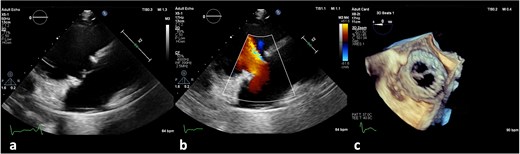

On the third day of hospitalization, transesophageal echocardiography revealed only moderate mitral regurgitation (Videos 3 and 4). However, on day 11, follow-up echocardiography showed a 7 × 18 mm vegetation on the prosthetic aortic valve, with a 5 × 7 mm floating formation (Fig. 2, Videos 5 and 6). By day 21, the vegetation had progressed, with a new formation on the tricuspid valve, an aortic annulus abscess, and worsened mitral regurgitation to severe (Figs 1 and 3, Videos 7 and 8). The development of double-sided endocarditis is very rare, and since the patient experienced it twice, congenital predisposing factors such as Patent Foramen Ovale and ventricular septal defects were ruled out. It was hypothesized that multiple predisposing factors ultimately led to the reinfection. Active IV drug use and its potential immunosuppressive effects, along with persistent poor dental condition and recurrent cutaneous infections, were identified as the main contributors, in addition to the patient’s overall non-adherence, for the development of double-sided endocarditis on two occasions.

Antero-septal paravalvular leak (PVL) of the prosthetic aortic valve in TTE (a) TTE PLAX (b), PSAX (c) 5CV (day 21 of hospitalization).

(a) Large vegetation on the neo-right coronary cusp of the aortic prosthetic valve in TEE LAX and (b) TEE SAX (day 11 of hospitalization).

(a) No vegetation, valve destruction of the prosthetic tricuspid valve on TTE RV inflow view, (b) No PVL of the prosthetic TV (TTE color doppler), (c) no signs of prosthetic IE on TV in TEE (day 21 of hospitalization).